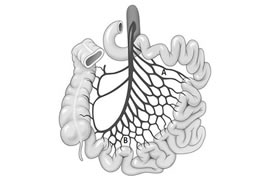

Το εκκόλπωμα του Μeckel είναι ένα αληθές εκκόλπωμα, μήκους 3-5 εκ, που εντοπίζεται στο αντιμεσεντερικό χείλος του ειλεού, συνήθως περίπου 60 εκ από την ειλεοτυφλική βαλβίδα. Αποτελεί εμβρυολογικό υπόλειμμα του ομφαλομεσενττερικού πόρου και απαντάται σε περίπου 2% του πληθυσμού και γίνεται συμπτωματικό σε 2% των περιπτώσεων. Αν και, συνήθως, καλύπτεται…